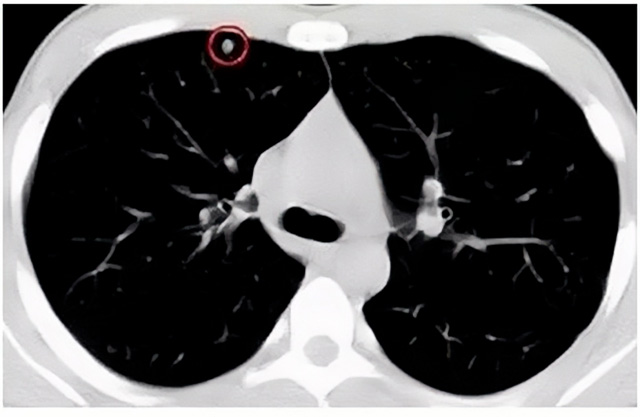

移动CT体检车可以检查肺结节发现早期肺癌

移动CT体检车可以做肺部检查。随着多层螺旋CT肺部低剂量扫描的临床应用,目前很多人选择肺部CT作为常规检查项目,较大地提高了肺结节的检出率。如果检查发现肺部有肺结节是磨玻璃型的,小于5mm的微小结节,大部分都是良性的。如果达到1CM以上的,很有可能有肺癌的机率。根据其内密度不同可分为磨玻璃结节、实性结节、部分实性结节。根据其大小可分为肺大结节、小结节和微小结节。如果是炎症性肺结节,几个月后复查有变化变小就不用做手术。如果CT再次复查结节没有变化,没有缩小就需要升级做病例检查。病理检查的确诊性是最高的。是有没患癌的标准。检查发现早的话,规范手术治疗,手术后5年的存活率很高的。肺癌这个要早发现早治疗。

现在的移动CT体检车的分辨率比X光高,CT扫描的图像越来越薄显像更清晰,检查更准确。得到了普及,肺结节的测出率很高的。但是伟德国际1949告诉大家,肺结节不等于肺癌。虽然很多是良性,但是很多肺癌都是肺结节发展来的。 必须定期检查复查。磨玻璃结节,肺癌的机率较高。肺癌是恶性肿瘤病死率最高的。除了环境,遗传,等因素。吸烟,从事烟雾工作行业的人员比较危险。发病比例高。肺部疾病早发现早治疗,依旧是肺部疾病的治疗标准。

一旦CT检查发现肺结节,若不规律复查,检查等同于白检。所以在复查中,如果结节中发现有增大的趋势,或大小发生了变化,我们必须提请注意及时治疗,不要掉以轻心。移动CT体检车的普及化,让肺部检查更准确更高效。发现肺结节时,及时就医并进行专业评估是确保准确分类和采取适当措施的关键。